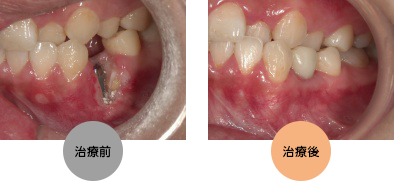

(骨が陥没した状態から治療しました)